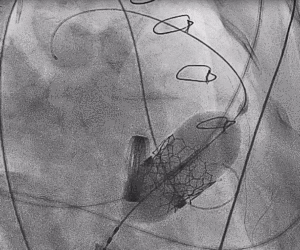

3.经股静脉入路送入16F E-sheath可扩张导管鞘,随后送入SAPIEN 3球扩瓣1输送系统,由于肺动脉入路朝上走,无需调弯,顺利跨瓣,将SAPIEN 3球扩瓣送入预定位置。精准定位后,以160次/分快速起搏,并保证1:1完全夺获,缓慢释放瓣膜。术后超声检查结果显示即刻跨瓣压差从术前9mmHg降至3mmHg,顺利完成瓣膜释放,回撤导管、导丝。

三尖瓣术前平均压差9mmHg

三尖瓣瓣中瓣术后平均压差3mmHg